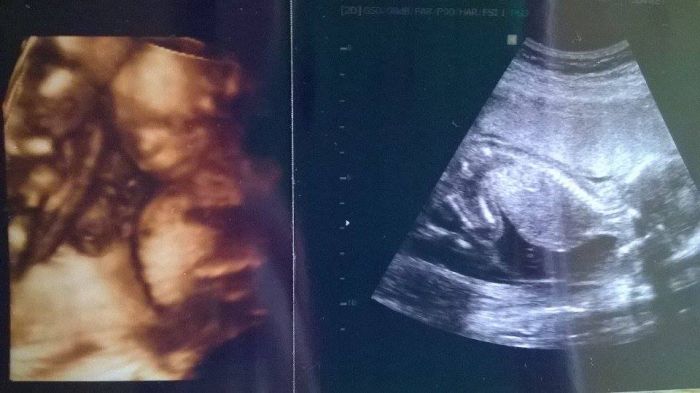

Holky, tak včera na UTZ zatím vše OK. Čekáme dva chlapečky

Příští týden máme velký UTZ, tam se dovíme podrobnosti